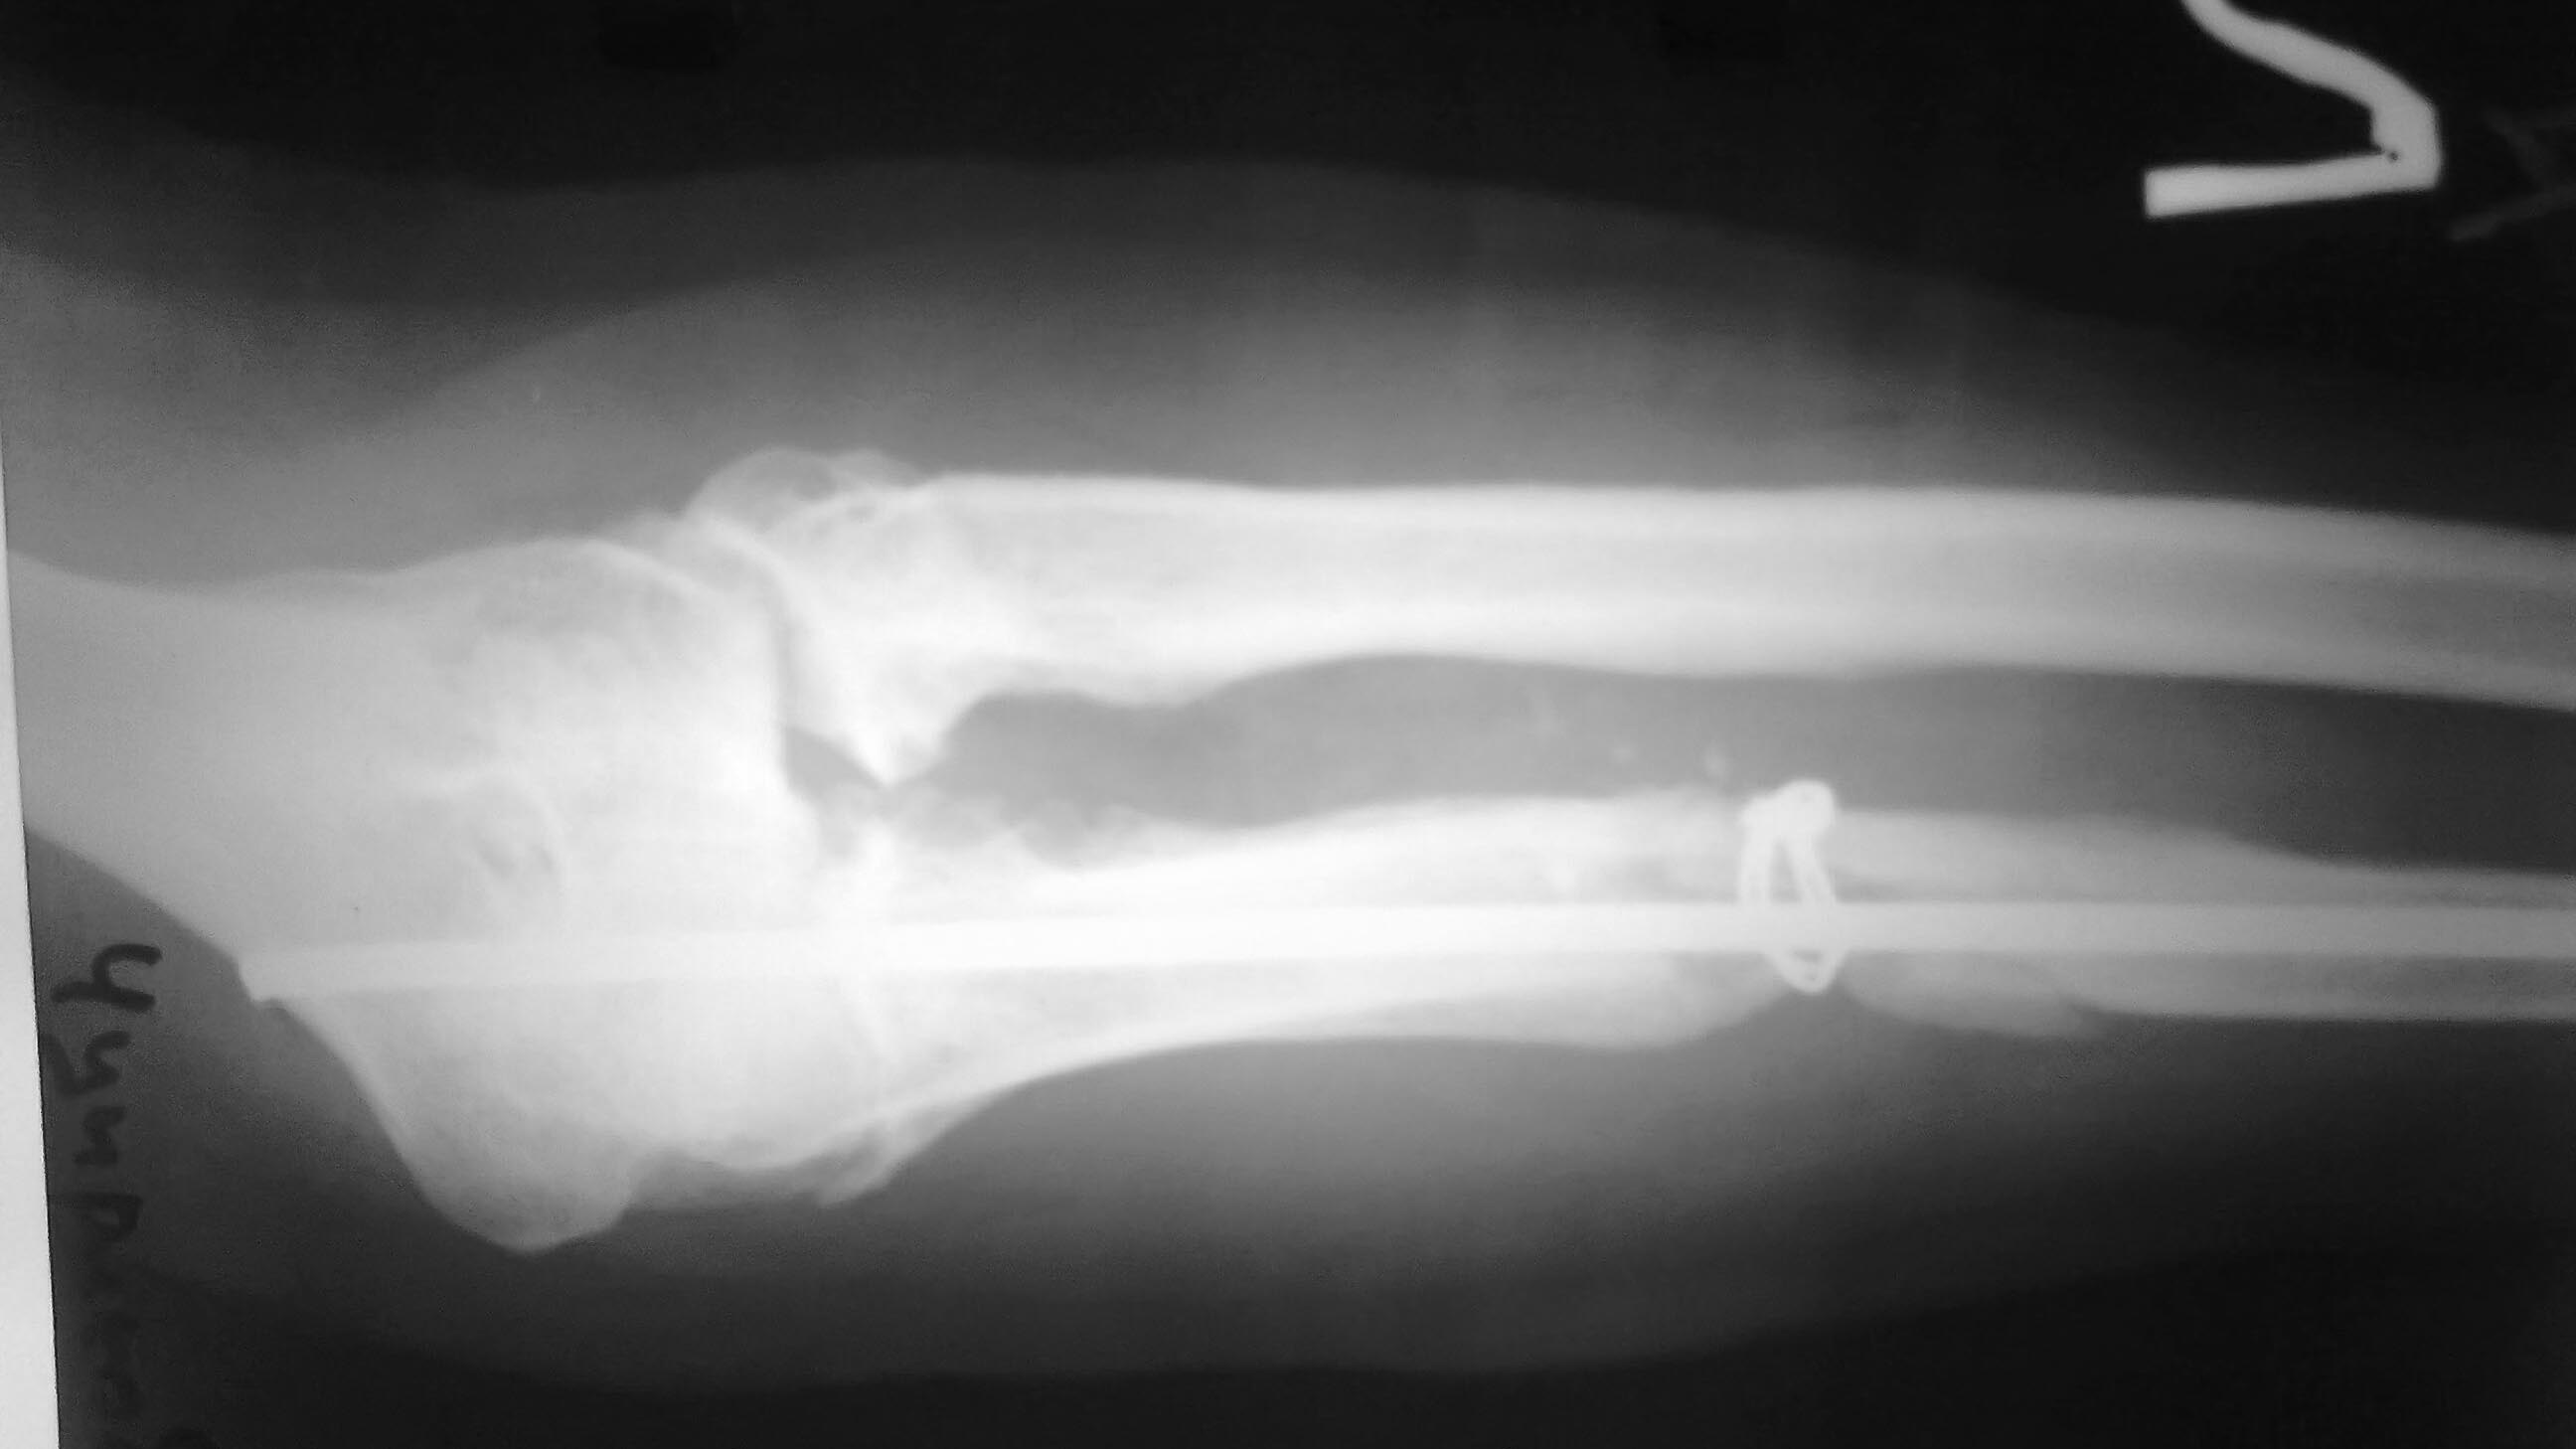

Ложный сустав локтевой кости. |

Больной оперирован 7 мес назад МОС локтевой кости гвоздем+непонятный серкляжик. Перелом не сросся металоконструкции удалены и больной в свободном поиске следуешего хирурга,да вот беда несколько стеснен в средствах. Локоть с его слов деформирован с юности(вывих головки лучевой кости, но до травмы обьем движений с его слов был полный). Сейчас стоит проблема выбора:1 вариант резекция головки и компрессия аппаратом Илизарова 2.Резекция головки луча и БИОС с компрессией локтевой кости3.Или сделать остеотомию локтевой и заместить дефек и не трогать головку луча. Подскажите оптимальный вариант.

А первый снимок сделан до остеосинтеза или после удаления фиксаторов? И зачем удаляли фиксаторы, если сразу не планировали реостеосинтез? "Непонятный серкляжик", вероятно, фиксировал костный трансплантат. Может и сросся бы такой перелом. Можно было поверх укрепить монокортикально блокируемой пластиной если конструкция была нестабильна. Не очень понятно, с какой целью Вы предполагаете остеотомию локтевой. При устранении углового смещения контакт между отломками, скорее всего, будет достаточным.

Да Сергей может быть и сросся бы,зачем удалили - не знаю(больной из другого города),и много чего можно было сделать.Но реку времени не остановить и не повернуть вспять.Так что давайте пожалуйста подумаем что делать сейчас.Между отломками никакого контакта нет и не будет(все что держал серкляж куда- то делось ,и теперь лучевая кость как распорка)

Почему Вы так уверены, что между отломками невозможно достичь контакта? Ведь даже при имеющемся угловом смещении на первом снимке диастаз между отломками отсутствует. Устранение углового смещения даст выигрыш в длине около 1 см. Если к этому добавить костную пластику, то вполне можно делать остеосинтез пластиной или любым другим фиксатором на Ваше усмотрение. Над резекцией головки луча я бы подумал 100 раз. Если до настоящей травмы локоть был подвижным и безболезненным, то наименее рискованный вариант - восстановить то состояние, которое было до травмы. То есть только выполнить остеосинтез локтя.

Вчера больной прооперирован - головку лучевой кости пришлось резцировать (сгибание было около 100 гр.и все бы ничего, но ось локтевой кости очень плохо выравнивалась ,сгибание после резекции увеличилось на 20 гр.) Снимок после резекции головки.

Головку использовали на аутопрансплантаты и попробовали поставить пластину.

А потом передумали, наложили два кольца, сделали остеотомию и интрамедуллярно армировали гвоздем, и начнем тянуть с 5х суток.